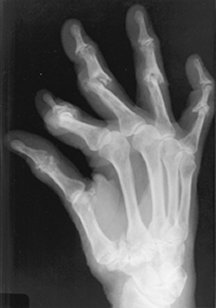

Robbin Baker, 32, of Poulsbo, Wash., was an avid tap dancer and horseback rider before she developed rheumatoid arthritis. Then, bouts of excruciating joint pain in her hands and feet made those pastimes impossible. Baker enjoyed a respite while pregnant

2 years ago, but she can’t fully participate in her daughter’s play activities because symptoms returned after childbirth.

When immune cells clash with cells in the skin of an individual with psoriasis, the skin cells divide unchecked and don’t properly mature, so excess layers of flesh scale and slough off. When immune cells attack joints, rheumatoid arthritis is the outcome. In lupus, which is formally called systemic lupus erythematosus, the immune system can attack multiple organs. In severe cases, both psoriasis and lupus can cause joint inflammation that results in arthritic damage.

The Japanese researchers, led by Ryo Yamada of the Institute of Physical and Chemical Research in Yokohama City, focused on a region of human chromosome 5. They examined 18 SNPs in 830 Japanese people with rheumatoid arthritis and 658 people without the disease. One SNP in a gene called SLC22A4 appeared more frequently in the participants with rheumatoid arthritis than in the healthy participants, the researchers found. That SNP makes RUNX1 bind unusually readily to SLC22A4, thereby suppressing it.

The researchers hypothesized that if altering the RUNX1 binding site in SLC22A4 affects how that gene behaves, so should changing the availability of the protein. Indeed, additional experiments have demonstrated a link between rheumatoid arthritis and a mutation in the gene that produces RUNX1.